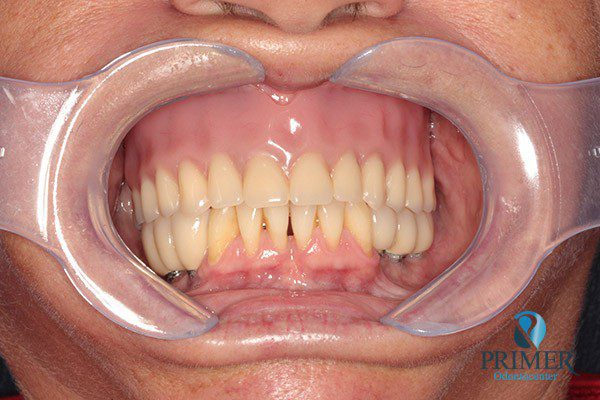

- Depois

- Sorriso final